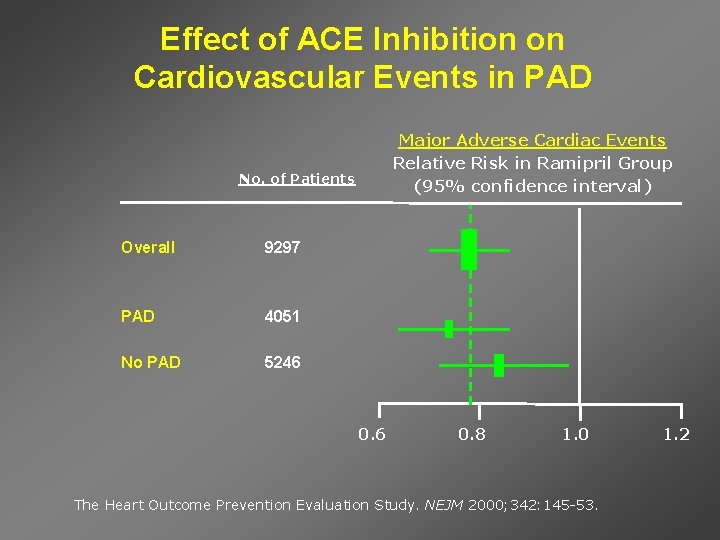

Effect of ACE Inhibition on Cardiovascular Events in PAD Major Adverse Cardiac Events Relative Risk in Ramipril Group (95% confidence interval) No. of Patients Overall 9297 PAD 4051 No PAD 5246 0. 8 1. 0 The Heart Outcome Prevention Evaluation Study. NEJM 2000; 342: 145 -53. 1. 2